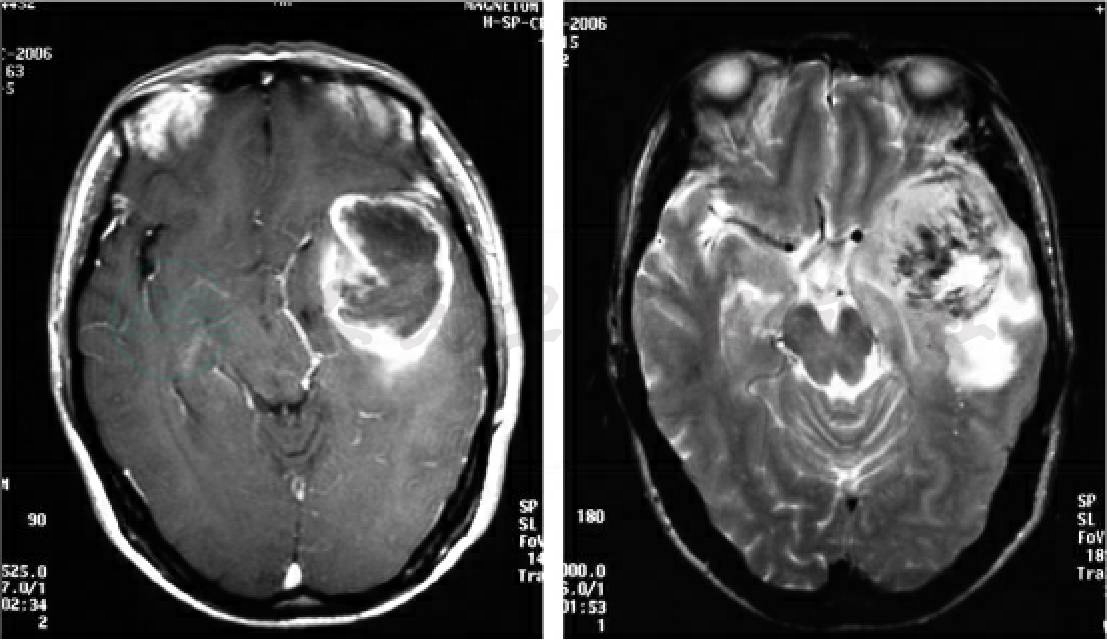

诊疗经过:入院后行MRI检查见左额占位病变,中间囊性坏死,有分隔,可见不均匀增强,瘤周大面积水肿。考虑胶质瘤Ⅱ~Ⅲ级(图3)。胸片、腹部B超结果未见明显异常。术前病例讨论:考虑恶性胶质瘤,不除外脑脓肿。入院后4天行手术,术中见肿瘤呈胶冻样,伴有坏死,术中冰冻为胶质瘤Ⅲ级,予切除肿瘤。

图3